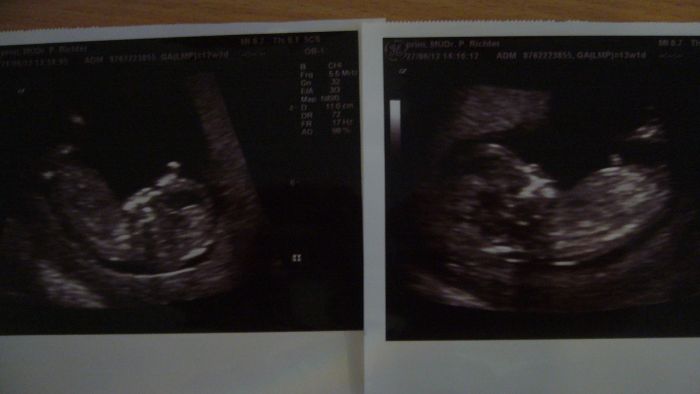

Vidím, že jsme všichni nervózní,já mám taky pořád strach. Protože už cítím pohyby, zas nervuju, že ho třeba i půl dne necítím, ale ono to je na začátku pohybů prý normální, tak si jdu vždycky lehnout a čekám..... Našla jsem si hudbu co se mu asi nelíbí, tak to vždycky pustím a za chvíli tam začne lítat. Taky jsem nervózní z toho čekání na výsledky triplů- v úterý a v pátek je jedu hodnotit na genetiku, budou mi dělat i ultrazvuk. Já snad zešílím, pořád na to myslím. Mám strach z plodovky- kdyby mi ji chtěli dělat, nevím. U nás v okolí dvoum řekli, že mají plodovku špatnou, děti si nechali- a jsou zdravé!!!!!!!Nechci to rizkovat.